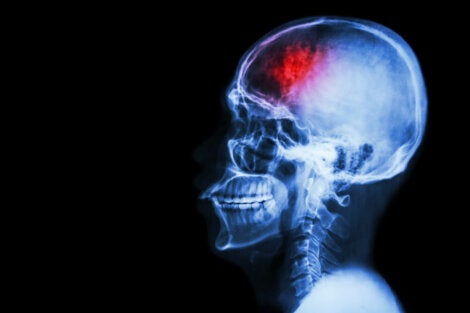

What’s a stroke?

A stroke is a sudden interruption or reduction in blood supply to the brain. It causes a combination of physical symptoms and cognitive changes that can be temporary or permanent.